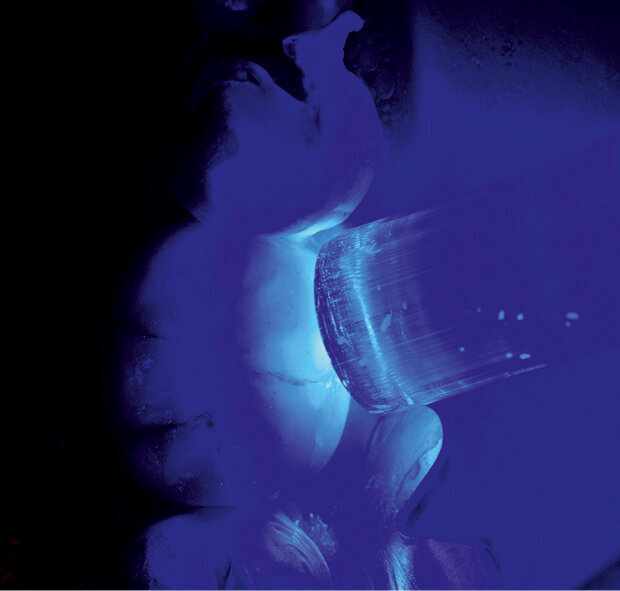

Fig. 9: Excess removal is easily achieved owing to the new technology based on the Ivocerin photoinitiator.

A 45-year-old male patient presented to the practice with a restoration on tooth #46. The tooth had been endodontically treated and temporised with a filling (Fig. 1). The temporary was removed, the tooth built up with Tetric N-Ceram Bulk Fill (Ivoclar Vivadent) and then prepared for the crown restoration (Fig. 2). An impression was taken with a one- step, two-phase impression technique using a putty and light-body silicone. After scanning the model, the crown was designed in the software suite (inLab, Dentsply Sirona) and milled from an IPS e.max CAD lithium disilicate block (Ivoclar Vivadent; Figs.3a & b). After the crystallisation fir- ing, the crown was stained and glazed (Fig. 4). The next step was to etch and silanate the ceramic crown with the new glass-ceramic primer Monobond Etch & Prime (Ivoclar Vivadent). This primer combines a ceramic etching and silanating component in a single material and therefore eliminates the need for the ceramic to undergo hydrofluoric acid etching (Fig. 5). After the etching and silanating step, the crown was rinsed with water and dried. The isolated enamel was then etched (Fig. 6). The adhesive (Tetric N-Bond Universal) was applied and dispersed with a strong stream of air. The dual-curing version of the Variolink Esthetic luting composite was used for seating owing to the thickness of the crown and the low translucency of the ceramic material (Fig. 7). The luting composite was applied into the crown. The restoration was then seated (Fig. 8) and light-cured from each side for two seconds. Excess composite was easy to remove owing to the Ivocerin photoinitiator (Ivoclar Vivadent), which provides a fast and thorough cure with a minimum amount of energy (Fig. 9). For final polymerisation, the restoration was light-cured from each quarter for 20 seconds (Fig. 10). Figures 11 and 12a & b show the oral situation after placement of the crown. Although the cement line was located above the gingival margin, it was not visible owing to the favourable tone and opacity of the luting composite. Figures 13a & b show radiographic control images of the restoration: the radiopaque build-up material and cement can easily be distinguished from the tooth structure. This aspect is particularly important in situations where excess cement cannot be seen with the naked eye.